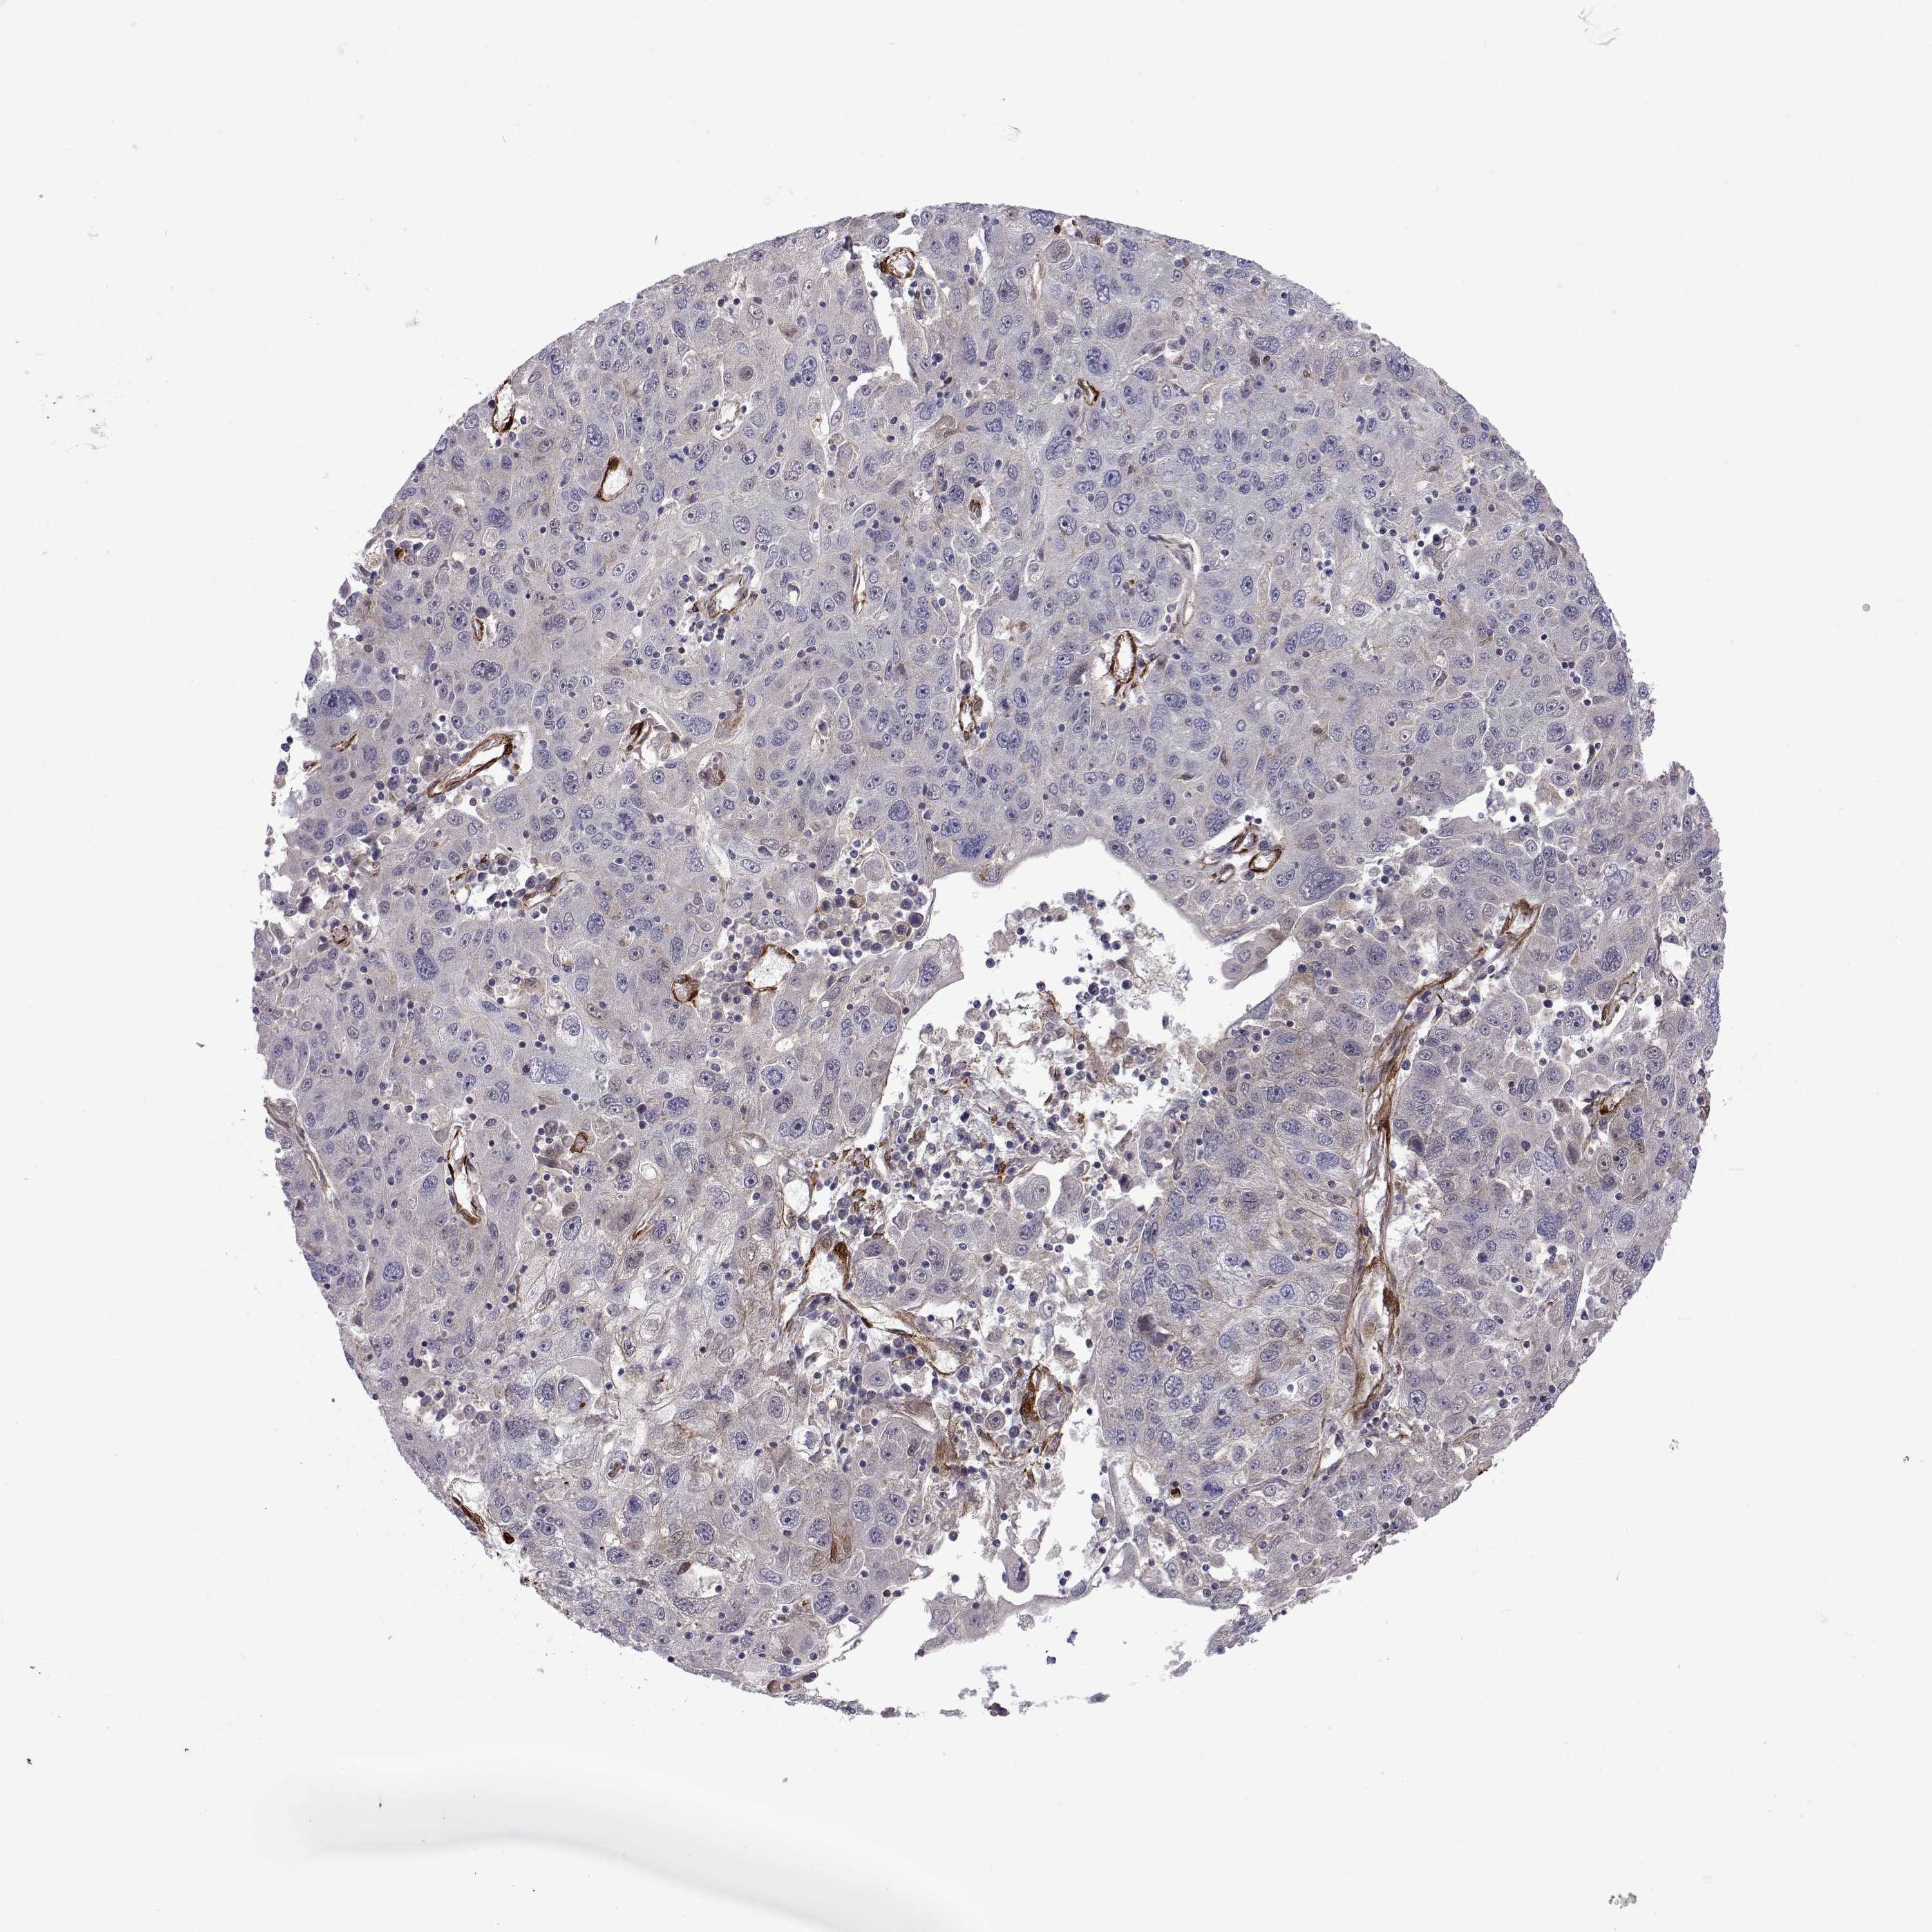

STOMACH CANCER - Protein expressioni

A mouse-over function shows sample information and annotation data. Click on an image to view it in a full screen mode. Samples can be filtered based on level of antibody staining by selecting one or several of the following categories: high, medium, low and not detected. The assay and annotation is described here.

Note that samples used for immunohistochemistry by the Human Protein Atlas do not correspond to samples in the TCGA dataset.

Antibody stainingi

Antibody staining in the annotated cell types in the current human tissue is reported as not detected, low, medium, or high, based on conventional immunohistochemistry profiling in selected tissues. This score is based on the combination of the staining intensity and fraction of stained cells.

Each image is clickable and will lead to virtual microscopy that enables deeper exploration of all samples and also displays staining intensity scores, fraction scores and subcellular localization as well as patient and tissue information for each sample.

Antibody HPA046862

Staining

High

Medium

Low

Not detected

Intensity

Strong

Moderate

Weak

Negative

Quantity

>75%

75%-25%

<25%

None

Location

Nuclear

Cytoplasmic/membranous

Cytoplasmic/membranous,nuclear

Adenocarcinoma, NOS